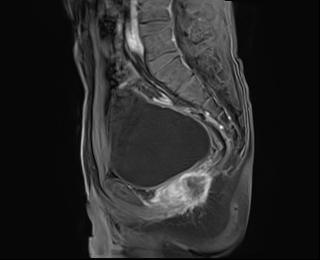

上圖為直腸癌術(shù)后復(fù)發(fā)患者。